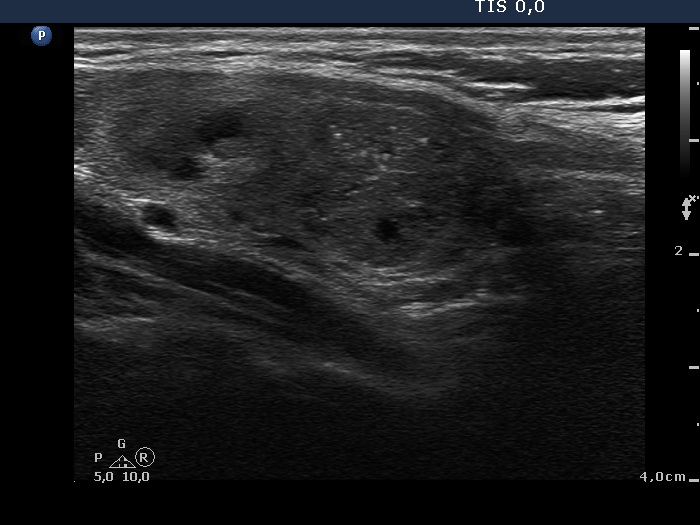

Intranodular hyperechogenic figures - case 951 (ultrasonographic picture 7)

Lower part of the right lobe, longitudinal scan. The hypoechogenic nodule has a lobulated surface.